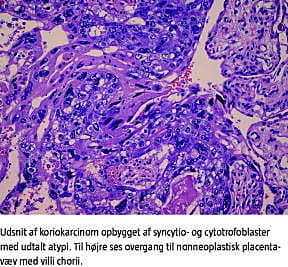

Placenta fandtes forstørret, ødematøs og bleg og målte 25,0 × 22,0 × 3,5 cm. Der fandtes normal navlesnor med tre kar og central incerering. Den føtale og maternelle overflade var upåfaldende. Ved mikroskopi fandtes imidlertid flere intraplacentære hæmatomer samt et område med koriokarcinom (der målte 3,0 × 3,0 cm). Tumorvævet var opbyget af cytotrofoblast og syncytiotrofoblast og fandtes med områdevise nekroser og hæmoragi. Tumoren strakte sig ned til den maternelle overflade med gennemvækst af decidua basalis.

Taksigelse: Overlæge Marianne Lidang , Patologiafdelingen, Herlev Hospital, takkes for det histologiske billede.